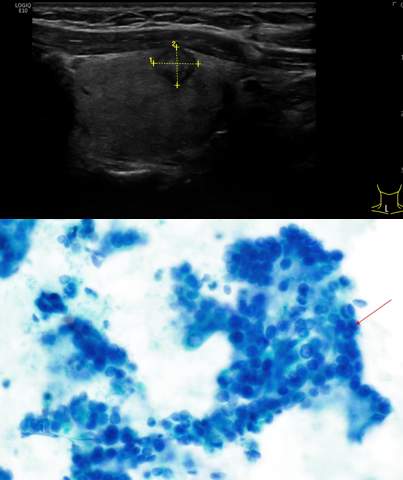

Nel nostro ambulatorio interno eseguiamo l’agoaspirato ecoguidato sui seguenti organi e lesioni:

• Tiroide

• Linfonodi

• Ghiandole salivari

• Mammelle

• Sarcomi di tessuti molli

• Lesioni cutanee/delle mucose